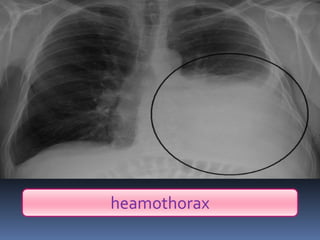

Abnormal Findings Un equalityof chest movement Dullness on percussion Decrease air entry Tachypenic heamothorax chest tube